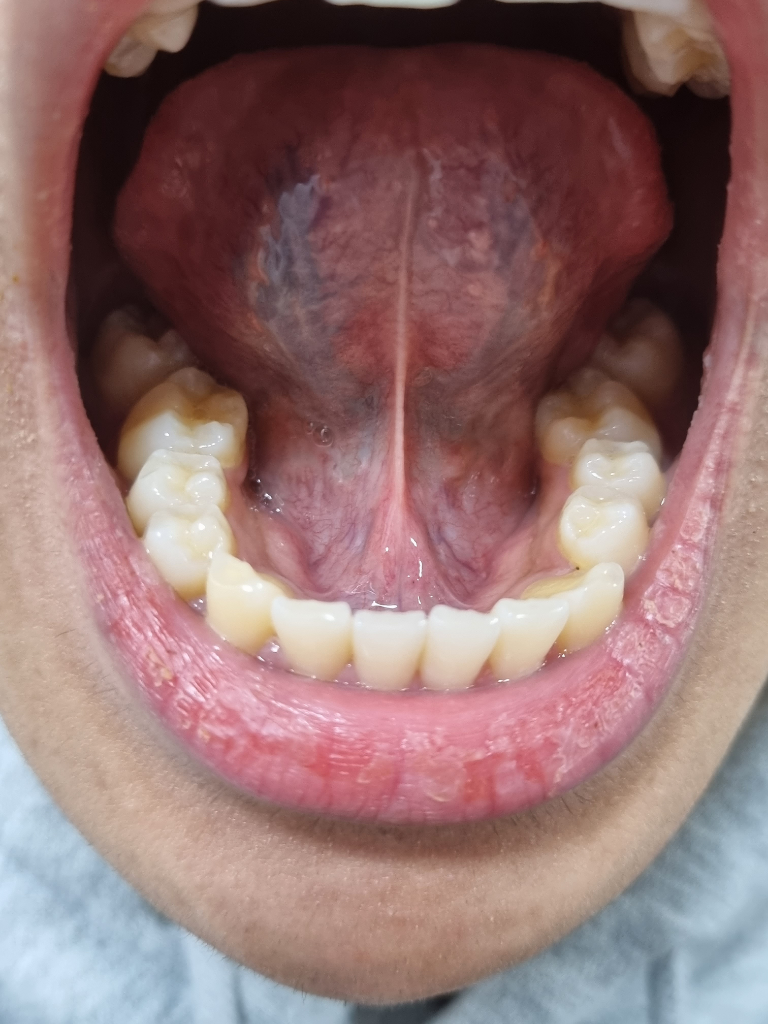

혀 밑에 흰 정도가 심한 거 같은데 문제가 있나요?

원래부터 이랬는지는 모르겠는데 요즘따라 혀 밑 부분이 하얀 정도가 좀 되는 것 같더라고요

이게 암 전조증상이라고 본 것 같은데 실제로 암을 의심해볼 정도인지 궁금합니다.

그리고 밑의 사진의 2번처럼 혀 밑 부분이 저렇게 나와있는데 며칠 전 치과에 내원했는데 이상 없다는 얘기를 들었습니다만 조금 불안합니다

+ 2번 부위에는 통증은 없는 상태입니다

저기에 보이는 부분들은 혀의 밑부분에 잇는 혈관들이 보이는겁니다. 크게 신경쓰지 않으셔도 될것같습니다.

정상적인 구조물이며 염증 및 붓기 등도 없습니다. 앞서 말씀드렸듯이, 본인이 혀를 들어서 평생 볼일이 없어 가끔 본인의 혀 밑을 보고 암이나 큰 문제라고 생각할 수 있으나 대부분은 정상적인 구조물입니다. 현재 말씀하시는 것도 정상적인 구조물입니다. 물론 지금처럼 너무 불안하다면 대학병원 방문 후 조직검사를 한번 해보시길 바랍니다.